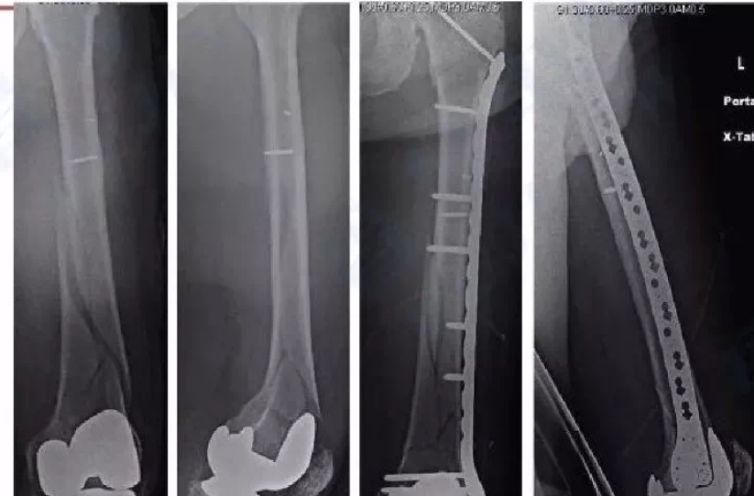

看似完美的内固定,为什么断裂?因为骨折存在间隙,钢板承担很大的弯曲应力最终疲劳断裂;钢板影响了骨的应力传导,骨折愈合慢了(此处有强大的内收力),竞争中钢板失败在先

点评:骨折不愈合与手术手法手术中剥离关系比较大;与受伤时的暴力软组织损伤有关:与固定方法有关。骨折不愈合,钢板必然断(引用图)

胫骨远端简单骨折选用钢板固定没有实现坚强固定,钢板承受应力,孔处应力集中断裂

更换长钢板后愈合

钢板的断裂是弯曲力和扭力所致,螺钉的松动拔出是因为固定物松动,骨折不愈合导致锁定钢板的断裂依然符合此原则